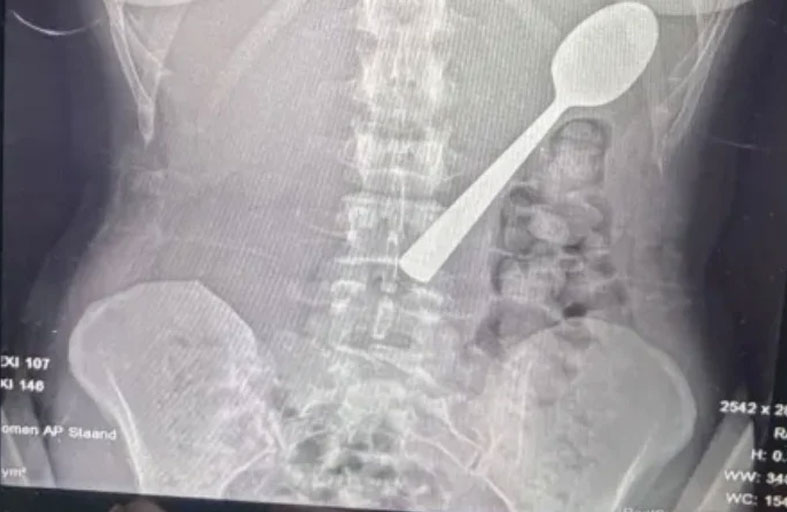

امرأة تبتلع ملعقة بالخطأ

تعرضت امرأة بلجيكية لموقف صادم بعدما ابتلعت ملعقة بطول 17 سنتيمتراً عن طريق الخطأ أثناء تناولها الطعام، وذلك بعد أن قفز كلبها على جسدها بشكل مفاجئ.

وقالت ريمي أملينكس، البالغة من العمر 28 عاماً، إنها اضطرت للاختيار بين الاختناق أو ابتلاع الملعقة، مشيرة إلى شعورها بأنها "انزلقت بسلاسة إلى معدتها".

وأضافت في تصريحات صحفية أنها كانت تجلس على الأريكة أثناء تناول الزبادي، وعندما قفز كلبها من نوع "هنغاريان فيزلا" المعروف بنشاطه، تفاجأت بشكل كبير ما أدى إلى انحشار الملعقة في حلقها بالخطأ، فحاولت إزالتها بيدها، لكن الموقف كان سريعاً جداً ولم يكن أمامها سوى ابتلاعها لتجنب الاختناق.

وبعد تناول العشاء، أدركت خطورة الموقف، وذهبت إلى الأطباء الذين أبلغوها أن الملعقة كبيرة جداً لتخرج طبيعياً، ما استدعى انتظار إجراء منظار معدة.

وأُزيلت الملعقة بعد يومين تحت التخدير الموضعي، حيث اضطر الأطباء لتدويرها داخل المعدة، ما تسبب في نزيف بسيط، وأكدت ريمي أن الحادث لم يترك أي أضرار دائمة، لكنها تعرضت لالتهاب في الحلق ونزيف في المعدة طفيف وحساسية لبعض الوقت.